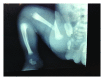

Cesarean section and right femur fracture: a rare but possible complication for breech presentation

Background. The breech extraction of the fetus through the vagina has a greater risk of hip fracture compared with the extraction by abdominal route. Case. A 2390 g female infant was delivered at 39 weeks by elective cesarean section for breech presentation. The newborn sustained a fracture of the right femur. A simple immobilization of the limb in extension led to a complete healing of the fracture without sequelae. Conclusion. Caesarean delivery reduces the risk of causing a traumatic injury of the newborn compared to vaginal delivery, especially with breech presentation but does not eliminate this possible accidental complication.